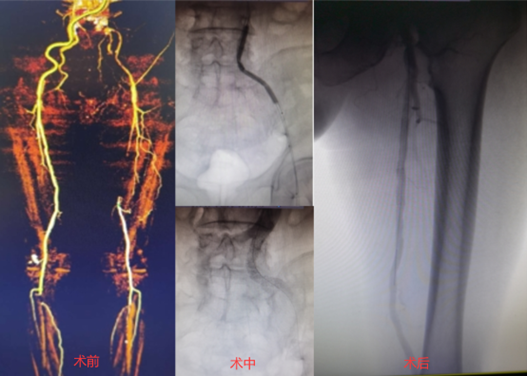

病例3:为Command 18联合Connect flex导丝顺利治疗的髂开口闭塞合并股浅长段CTO病变;术中首先采用逆向技术,穿刺股总动脉,开通髂动脉;随后使用Connect flex导丝顺利开通股浅远端长段CTO病变。